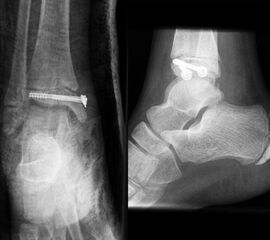

THERAPIE

Behandlungsziel ist die exakte Rekonstruktion der Gelenkfläche sowie die Minimierung des Risikos einer späteren Wachstumsstörung. Dislozierte Frakturen werden offen reponiert, die Osteosynthese erfolgt mit einer Kleinfragmentschraube. Finden sich viele kleine Fragmente kann eine K-Draht Osteosynthese durchgeführt werden. Wird der Innenknöchel operiert, kann bei gleichzeitiger hochgradiger lateraler Instabilität eine Rekonstruktion des lateralen Bandapparats durchgeführt werden. Fibula Frakturen stellen sich meist spontan ein, sodass hier keine zusätzliche Osteosynthese notwendig ist.

Nach der Osteosynthese wird die Fraktur für ca. vier Wochen in einem Unterschenkelgips ruhiggestellt. Bei Schmerzfreiheit der Frakturzone erfolgt anschließend eine schmerzadaptierte Belastungssteigerung über weitere zwei Wochen. Sobald unter Alltagsbedingungen Beschwerdefreiheit besteht kann die sportliche Belastung langsam gesteigert werden. Kirschnerdrähte werden 6-8 Wochen postoperativ, Schrauben nach zwölf Wochen entfernt. Es empfiehlt sich klinische und radiologische Kontrollen im Abstand von 6 Monaten bis zum Wachstumsabschluss durchzuführen, um ein mögliches Fehlwachstum frühzeitig zu erkennen.